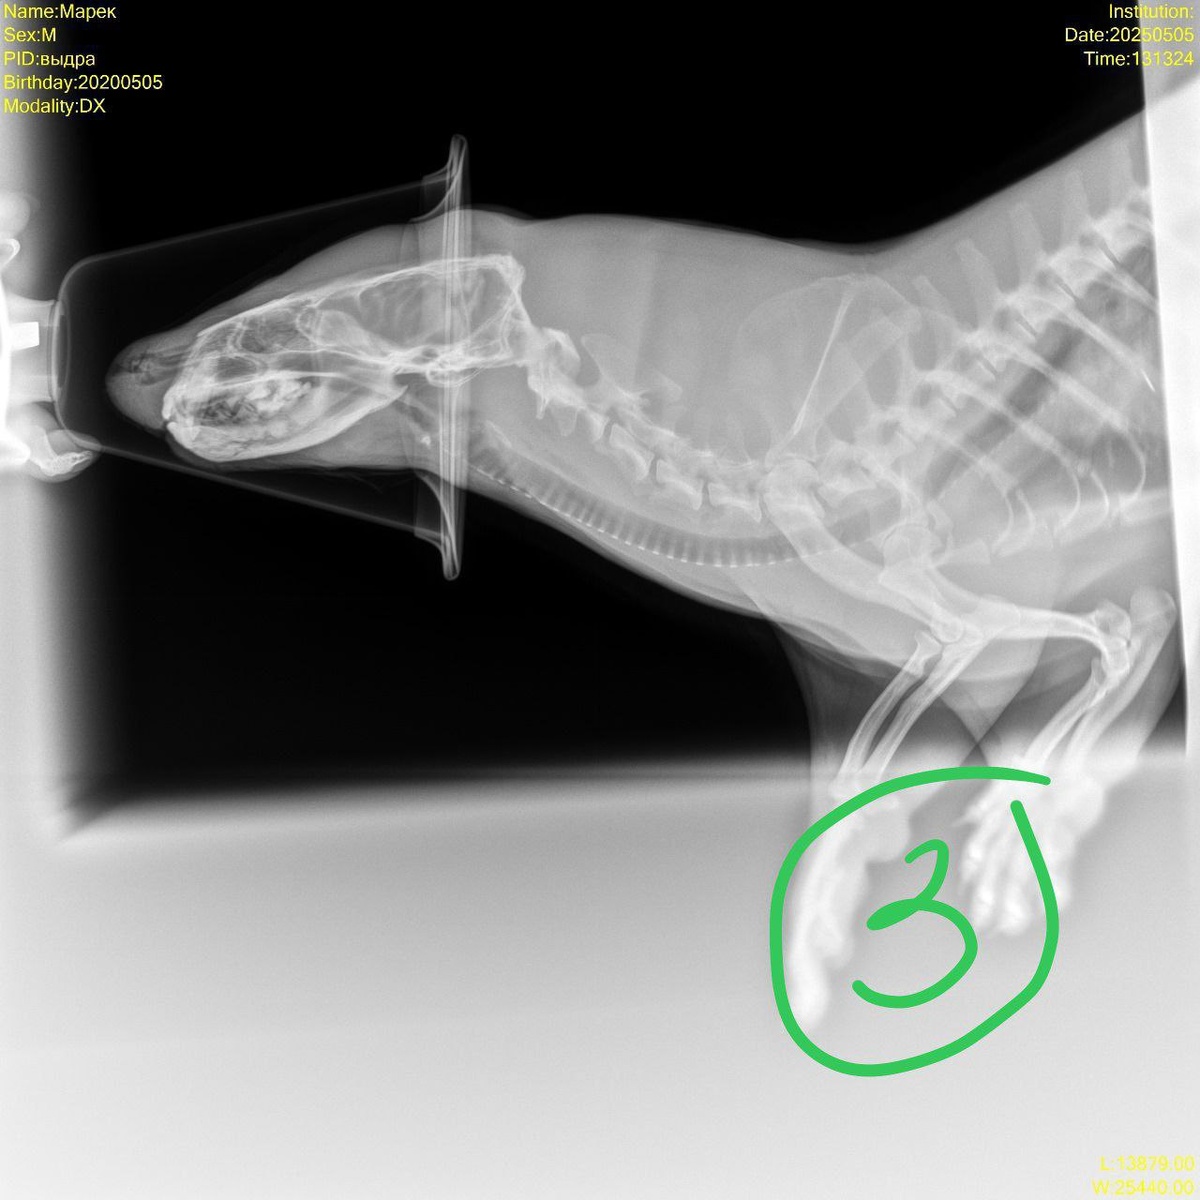

Сейчас будет оригинальное вступление: начались как-то у выдры Марека зелёные сопли.... Идут и идут! Два месяца Марек периодически ходит с бахромой из носа (на этом месте родители дошколят вздрогнули😁) — непорядок! Обследовали — никаких проблем не нашли. Что делать? Дали антибиотик. Как будто помогло, но ненадолго. Решили: хватит полумер, пора браться за мареков нос по полной программе! Позвали коллег из КГТУ и ветеринарной клиники, разложили красавца и давай его исследовать. Конечно, дали наркоз, потом сделали рентген. И уж на рентгене обнаружили корень проблемы: «сопливил» воспалённый клык на верхней челюсти! Не откладывая, провели стоматологическую операцию, клык благополучно удалили, и сопли тут же прошли. А Марек как-будто ничего и не заметил!😁❤️

Конечно, дали наркоз, потом сделали рентген. И уж на рентгене обнаружили корень проблемы: «сопливил» воспалённый клык на верхней челюсти! Не откладывая, провели стоматологическую операцию, клык благополучно удалили, и сопли тут же прошли.